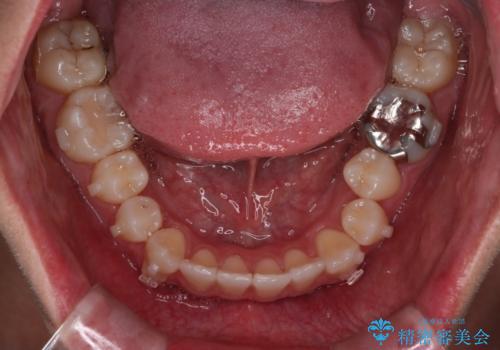

- 右上2番が欠損しており、歯並びをバランスよくしたいということで来院されました。

ワイヤー装置とマウスピースで悩まれていましたが、マウスピースで治療可能と判断致しましたのでマウスピースにて治療しました。

IPR、歯列弓拡大、ゴム掛けを行い歯並びを整える治療計画を立てました。

右上2番が欠損しているため、見た目と噛み合わせの両方のバランスを整えるために経過を追いながら必要な部位にゴム掛けをしました。

また矯正後、患者様の希望で

メタルインレーをセラミックインレーにやりかえさせていただき、さらに綺麗に仕上がりました。